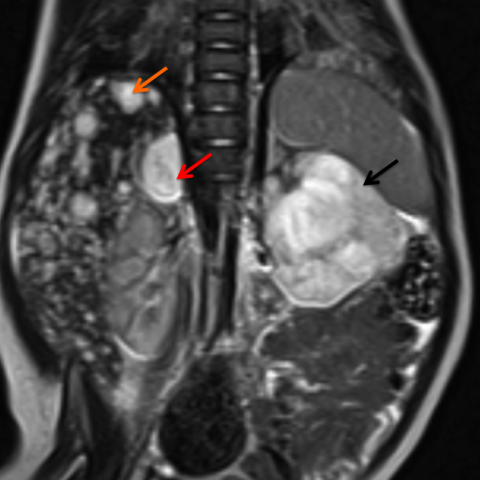

Main differences between Wilms and Neuroblastoma

Calcifications and metastasis to bones in neuroblastoma

Invasion of vessels and well defined in Wilms (neuro encases and is irreguar)

4 years in Wilms and 2 years in Neuro